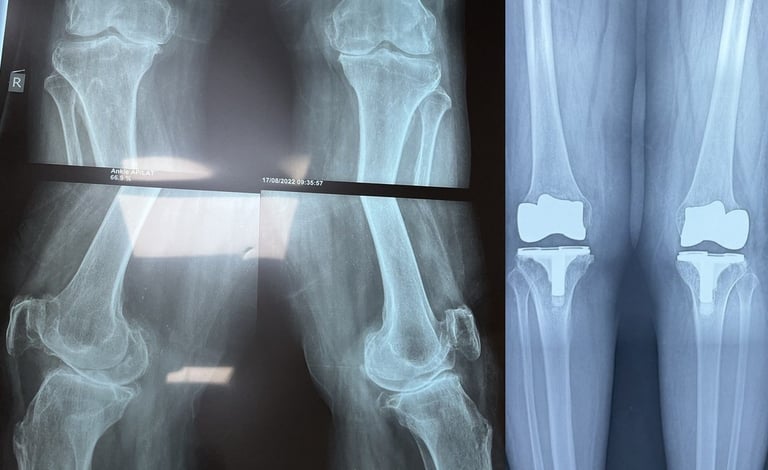

Joint Replacement

Advanced techniques for knee and hip replacements ensuring quicker recovery and improved mobility.